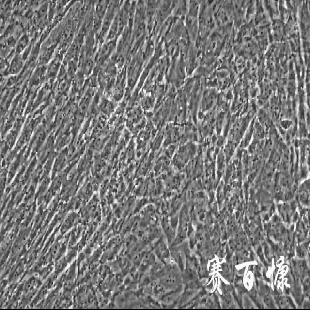

5)細(xì)胞生長(zhǎng)方式:上皮樣細(xì)胞,貼壁培養(yǎng)。